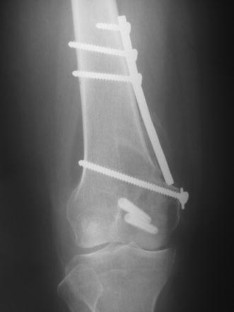

Fig. 2